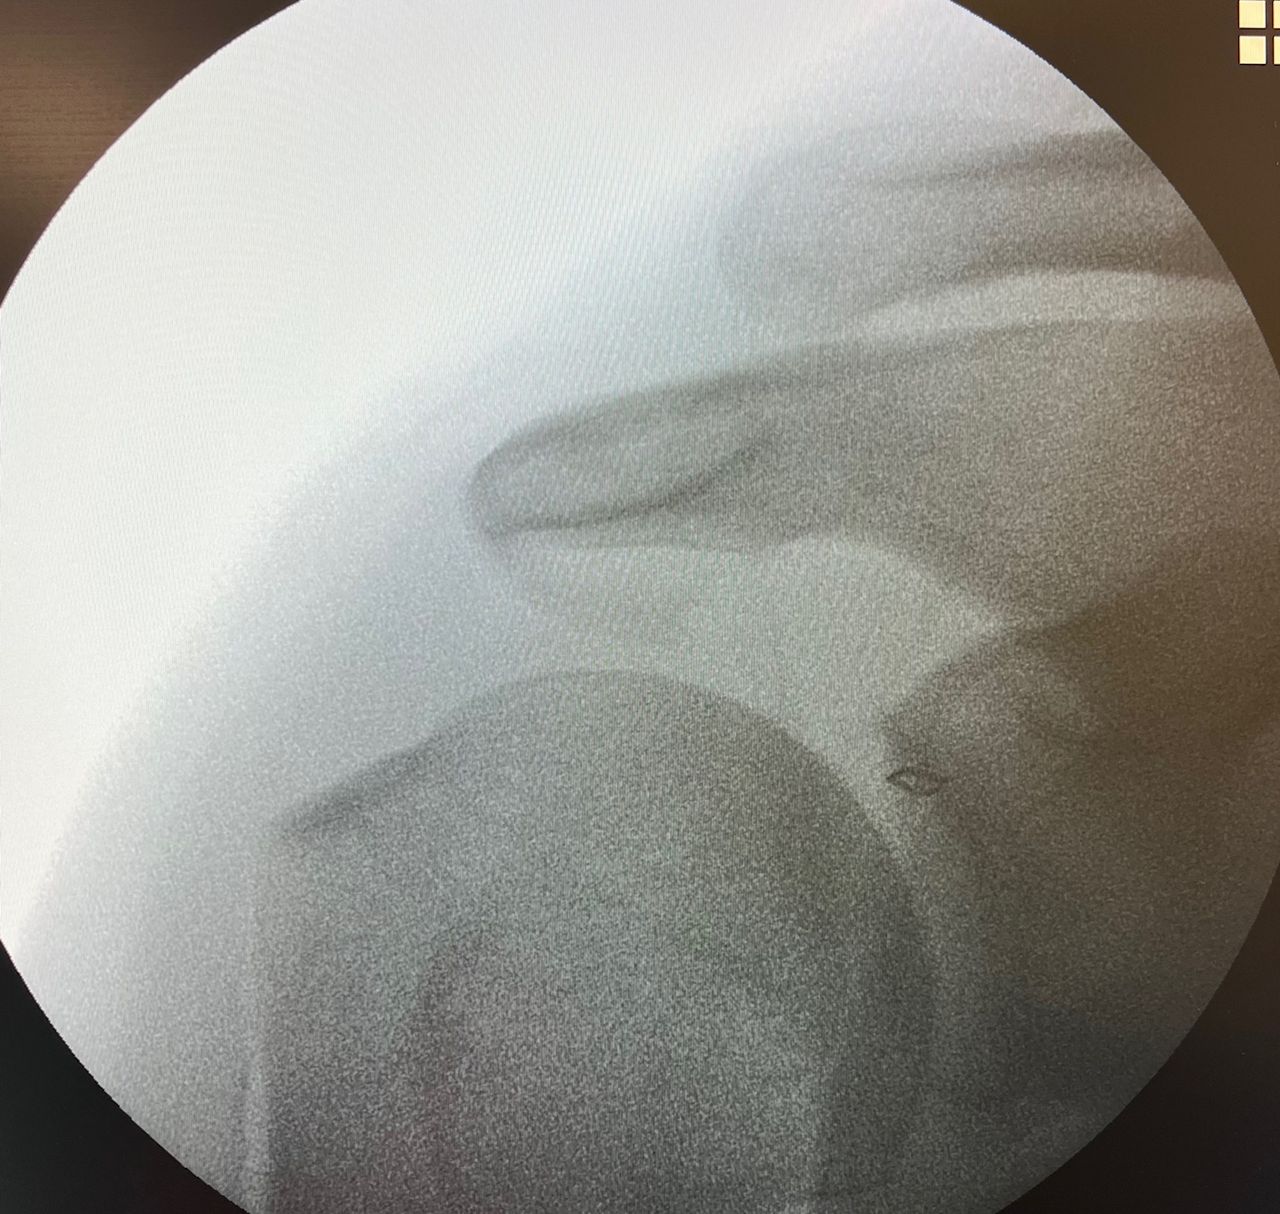

Fotos y vídeos